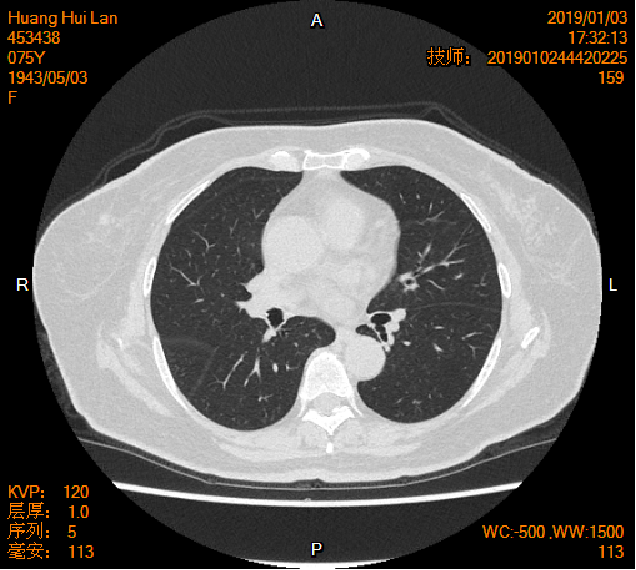

2019-01-04胸腹盆CT